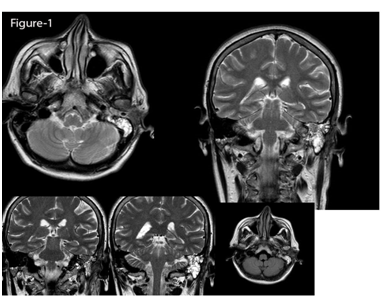

In MRI with and without IV gadolinium injection: an enhancing mass measuring 22*10*8mm was present in the middle ear and in the mastoid antrum. Minimal intracranial extension through erosion of the tegmen tympani was visible. Abnormal thickening and enhancement of the lining of the EAC was visible too which may indicate tumor extension (Figure 1). Informed Consent was obtained through a signed permission form. The patient underwent surgery on November 2012. At surgery, the tumor was soft and creamy and encapsulated and was separated from adjacent. The tumor was not removed en bloc. The ossicles and tympanic membrane were preserved intact. Histologically, a polypoid neoplastic lesion covered by stratified squamous epithelium composed of glandular structures, lined by two layers of bland looking luminal epithelial cells and basal (myoepithelial) cells. Immuno-Histo-Chemical Examination (IHC) showed positive reactivity for CK in epithelial cells as well as positive reactivity for S100, SMA and p63 in myoepithelial cells. Neither atypia nor mytosis were seen. Finally, pathology report was benign epithelial myoepithelial tumor. These histopathological findings were indicative of myoepithelioma.

Figure 1 MRI with and without IV gadolinium injection: an enhancing mass was present in the middle ear